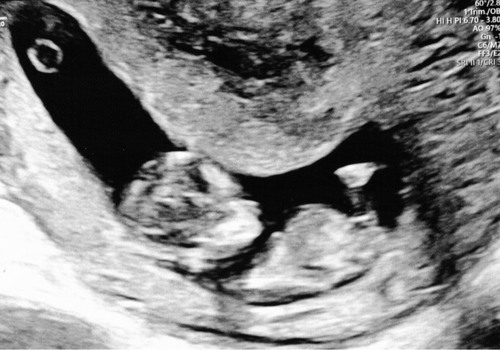

Wat denken jullie? 10+4🥰

Wie waagt de gok? 🩵🩷 10+4